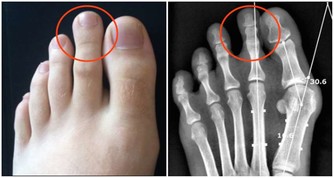

久之這些重金屬就會在腎小管內聚集,嚴重時甚至會引起腎小管的壞死。

但這個藥有個很大的毒副作用,就是損傷腎臟,像氨基糖甙類抗生素一樣,引起腎小管壞死。

我們吃下去之後,這些重金屬就會沉積在我們的腎小管內,久而久之,就會傷及我們的腎臟。